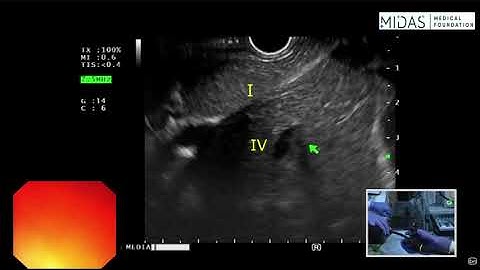

EUS For Beginners with Dr. Saurabh Mukewar Part - B